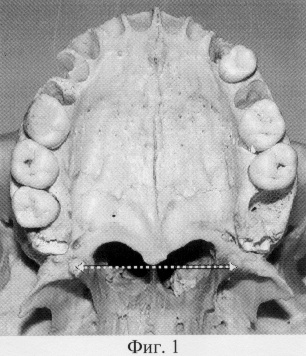

Рентгенография небного шва: Медицинские исследования и диагностика